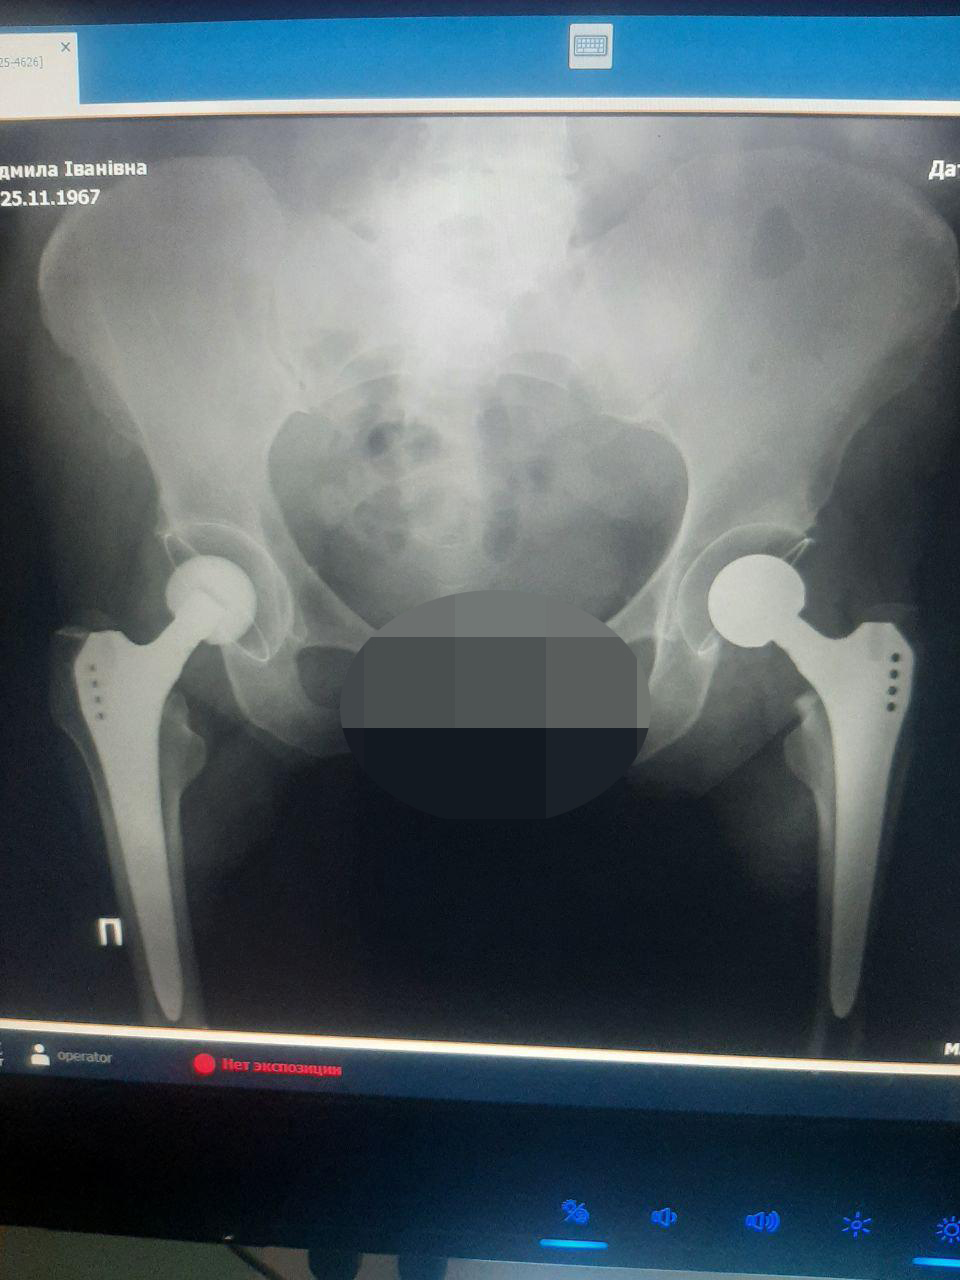

Перша операція тотального ендопротезування кульшового суглоба відбулася цього тижня. Пацієнтка, жінка 1967 року народження, поступово повертається до активного та здорового життя. Така хірургічна операція вважається однією з найскладніших. Хворому встановлюють штучний суглоб, який імпактується в кістку, дозволяючи відновити втрачену функцію кінцівки. Проводиться обробка кульшової западини та стегнової кістки. У кульшову западину вставляється вертлоговий компонент, а в стегнову кістку – ніжка ендопротезу.

У лікарській бригаді травматолого-ортопедичного відділення «Охтирської центральної районної лікарні» (завідувач Артем НАДЖИБУЛЛА) є професійна та досвідчена команда ортопедів-травматологів, анестезіологів, операційних медсестер та сучасні технології. Адже успіх операції по заміні суглобів залежить від кожного спеціаліста.